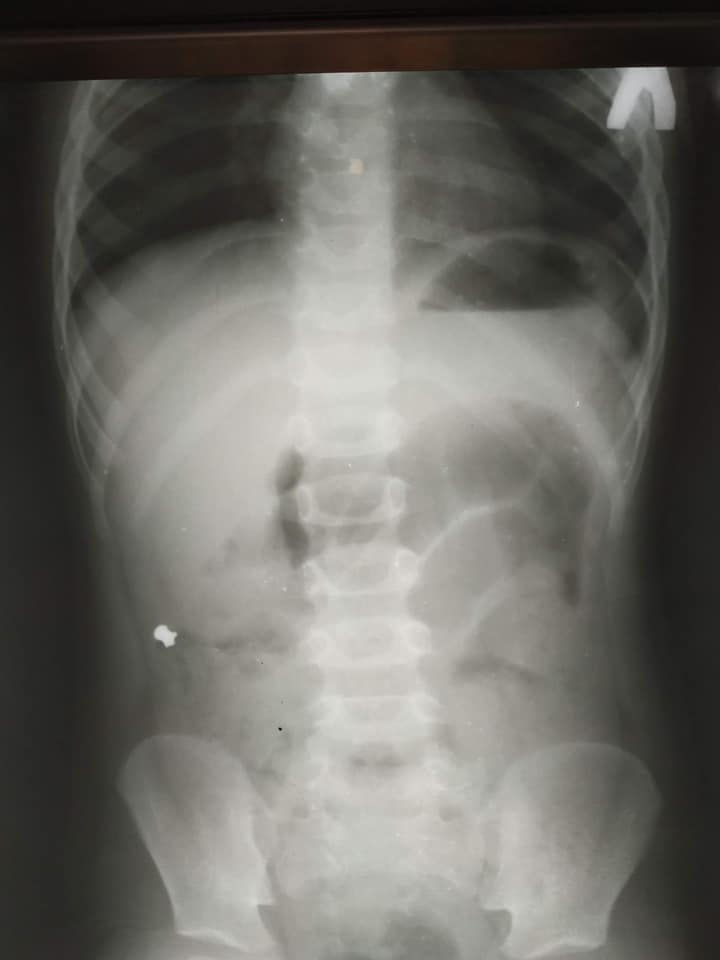

До львівської обласної дитячої лікарні ОХМАТДИТ «швидка» привезла 6-річного хлопчика з болями у животі. У дитині діагностували гострий апендицит, та не рентгені виявилось, що в апендиксі є куля від травматичної зброї. Про це 1 лютого повідомили на сторінці лікарні.

Дитячий хірург Кирило Лапшин, який чергував цього дня, дуже здивувався рентген-знімку маленького пацієнта. Справа, у клубовій ділянці, чітко візуалізувався дивний сторонній предмет, в обрисах якого лікар впізнав кулю від пневматичної гвинтівки.

І все б нічого, якби куля потрапила зі шлунка в кишківник і вийшла. Однак у хлопчика куля опинилася у червоподібному відростку (апендиксі), що стало причиною запального процесу у ньому і вклало дитину на операційний стіл.

Хірурги терміново виконали лапароскопічну апендектомію – видалили запалений апендикс через три маленькі проколи у животі.

«Коли ми видаляли апендикс, я зразу побачив, що в ньому є потовщення. Ми його видалили і вже назовні розрізали. Там справді була куля! Вона, як стороннє тіло, потрапила з кишок у апендикс і створила його обструкцію. Це і стало незвичайною причиною апендициту», – розповів дитячий хірург Кирило Лапшин.